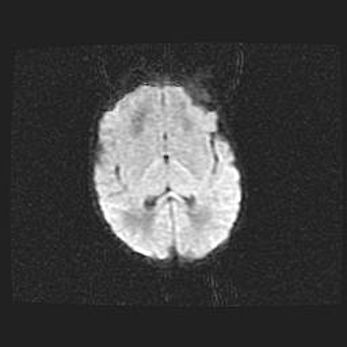

Лейкомаляция с кистозно-глиозной дегенерацией головного мозга.

Возраст: 2 месяца 25 дней

Вес: 6400 г

Окружность головы: 40 см

Срок гестации: 41 неделя

Лейкомаляцию относят к ишемически-гипоксическим повреждениям головного мозга, диагностируемым у новорожденных. При лейкомаляции в головном мозге обнаруживают очаги некроза, возникшие после тяжелой гипоксии и нарушения кровотока. В процессе морфогенеза очаги проходят три стадии: 1) развития некроза, 2) резорбции и 3) формирования глиозного рубца или кисты. Перивентрикулярная лейкомаляция (ПЛ) встречается примерно в 12% случаев среди новорожденных, обычно – у недоношенных детей, причем, частота ее зависит от массы, с которой младенец появился на свет. Наибольшее число малышей страдает лейкомаляцией, если масса при рождении 1500-2500 г.